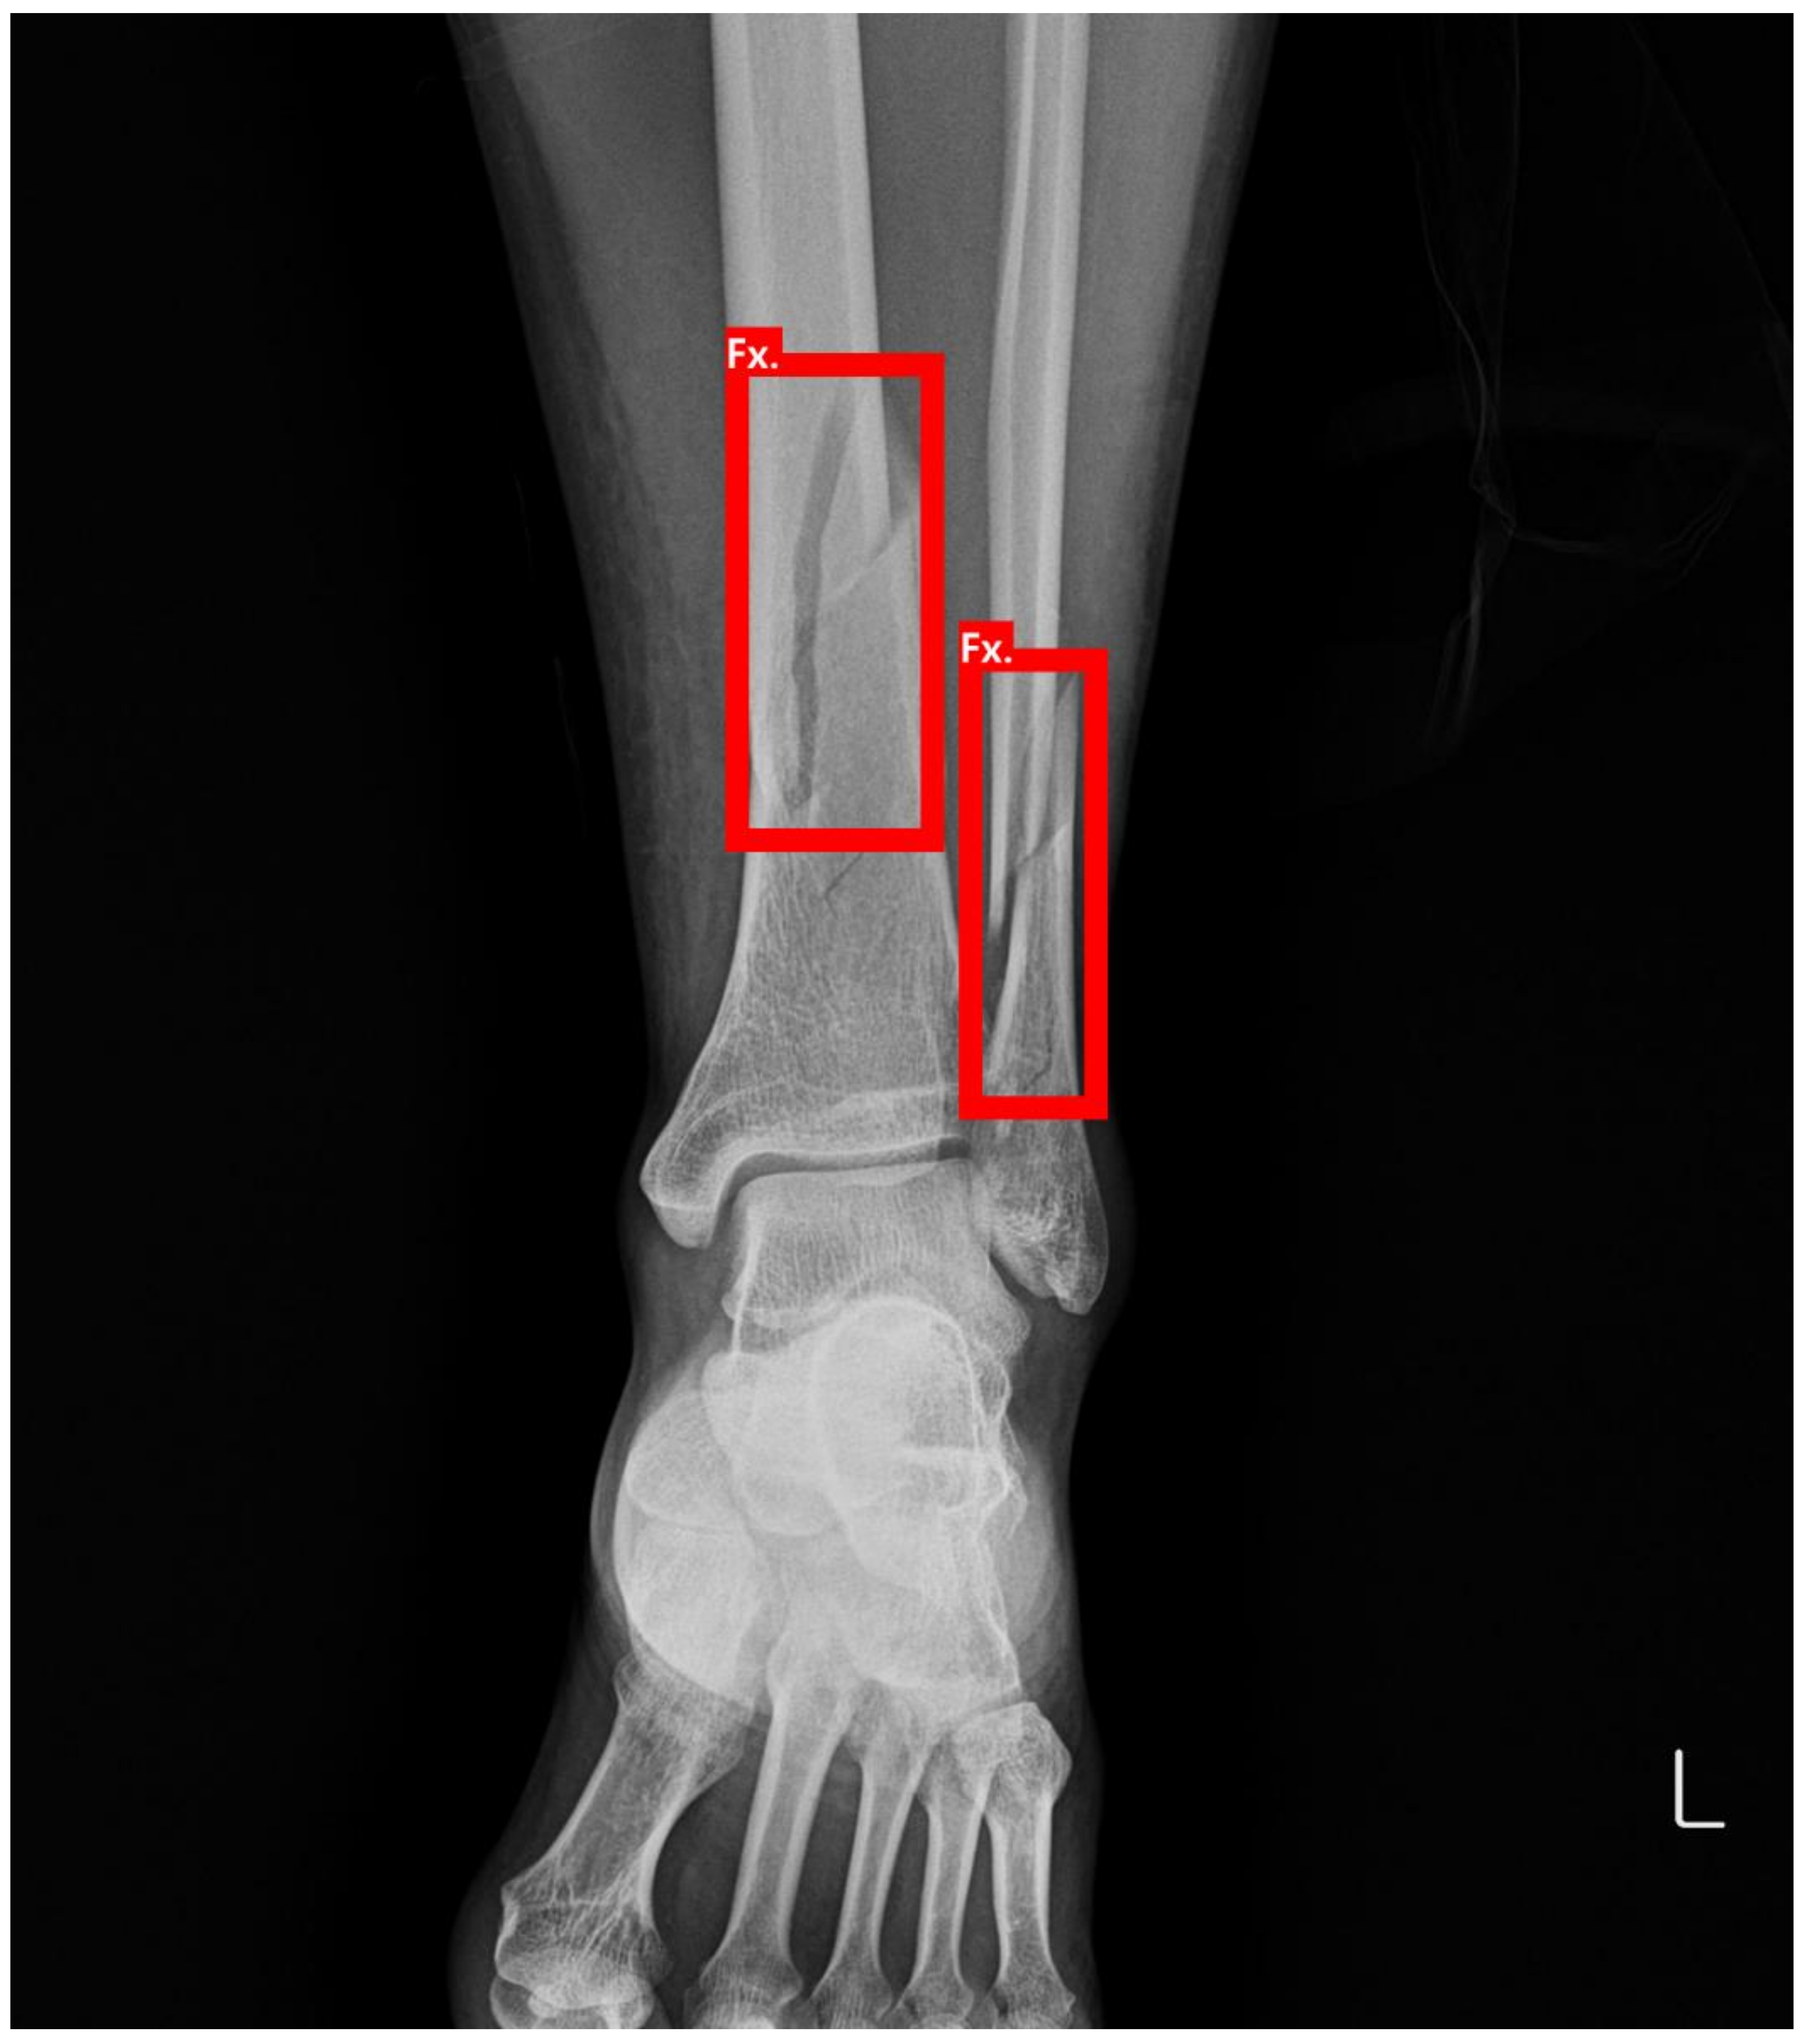

Detecting Ankle Fractures in Plain Radiographs Using Deep Learning with Accurately Labeled Datasets Aided by Computed Tomography: A Retrospective Observational Study

2.1.1. Dataset Preparation